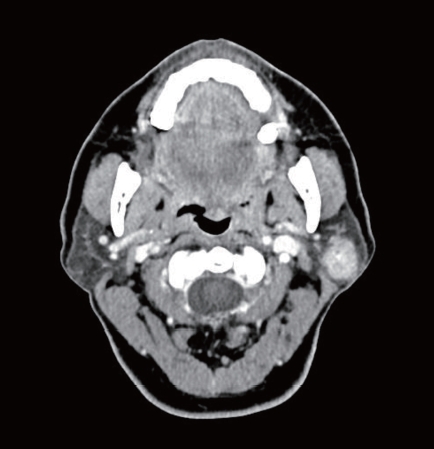

58세 여환에서 좌측 이하선 천엽에 국한된 2 cm 고형성 종괴가 관찰되었다. 이하선 천엽절제술 시행 후 조직검사상 선방세포암종(acinic cell carcinoma)으로 확인되었다. 절제연에서 종양은 관찰되지 않았으며 영상검사상 전이로 의심되는 소견은 관찰되지 않았다. 향후 치료를 위한 적절한 조치는?

① 추가 치료 없이 추적 관찰

② 이하선 심엽 절제술

③ 방사선 치료

④ 동시항암 방사선 치료

⑤ 예방적 경부 절제술

이하선 천엽에서 발생한 초기의 저악성도 얌종에서는 이하선천엽절제술을 시행한다.